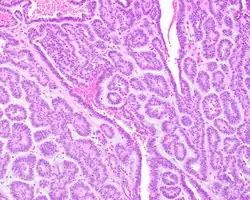

Canalicular adenoma growths are usually small at the time they are noticed, with an average size of about 1.6 cm.[1] Their histologic appearance is very distinct, with a channel-like pattern between cords and ribbons; the pattern has been described as resembling a "string of pearls."

The growths often contain are often small bight squamous balls, or morules. They also typically contain a well-developed supporting tissue - a fibrous stroma - which is rich in hyaluronic acid and chondroitin sulphate.[1] In a few cases, the growths may contain small calcium deposits or microliths. Although it is seldom necessary, a pathologist can confirm the existence of canalicular adenoma through immunohistochemistry studies, with the cells reacting with pancytokeratin, S100 protein and SOX10, with a delicate GFAP reaction around the periphery.[5][1][6][7] Although it is a benign tumor, a positive diagnosis of canalicular adenoma may be necessary to exclude the existence of other medical conditions such as a basal cell adenoma, pleomorphic adenoma, adenoid cystic carcinoma, and polymorphous adenocarcinoma.